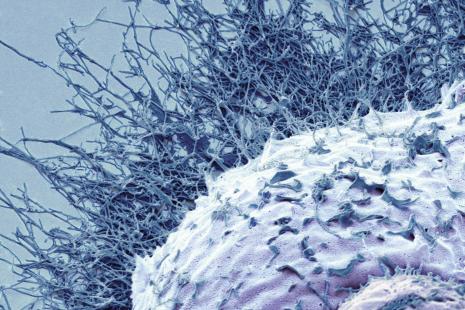

Produire une particule non infectieuse imitant le virus cible

L’idée de la biotech est d’utiliser les plantes vivantes comme bioréacteurs afin de produire une particule non infectieuse imitant le virus cible. Outre la grippe, Medicago développe différents types de vaccins à l’aide de sa technologie exclusive Proficia, y compris contre le Covid-19.